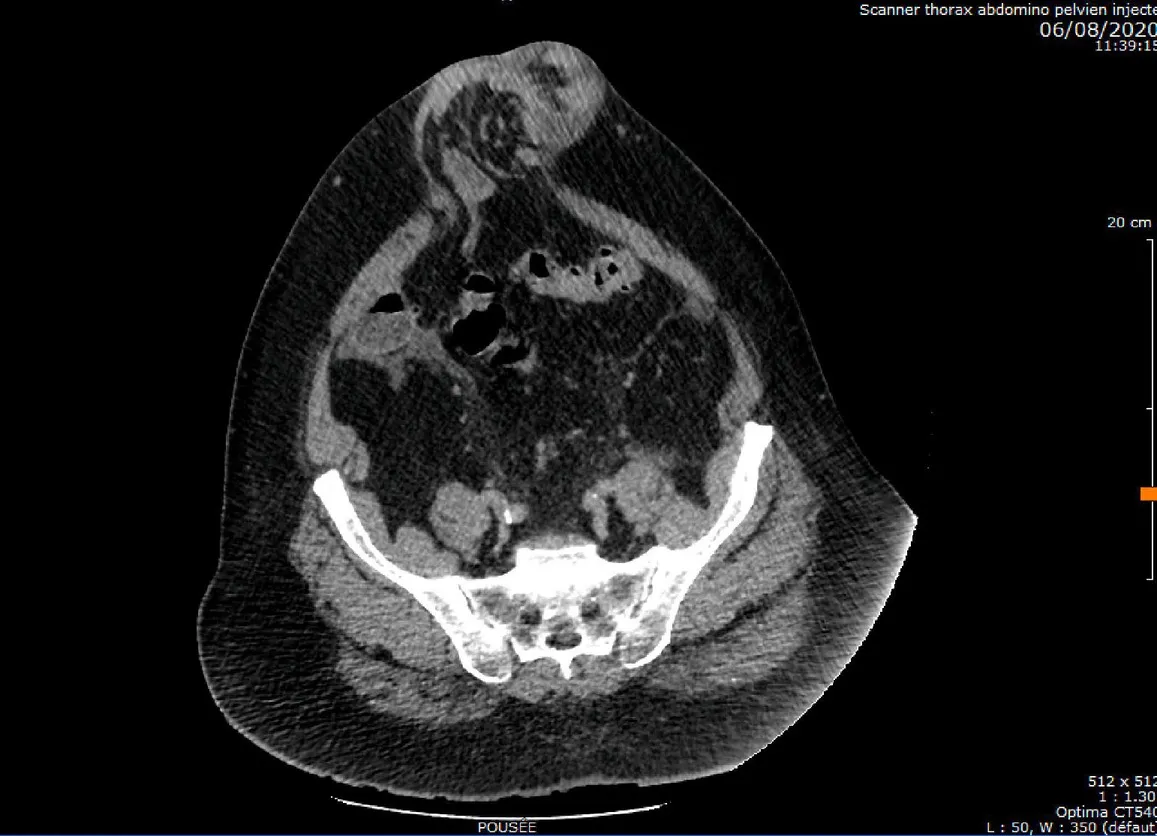

TAC di un’eviscerazione